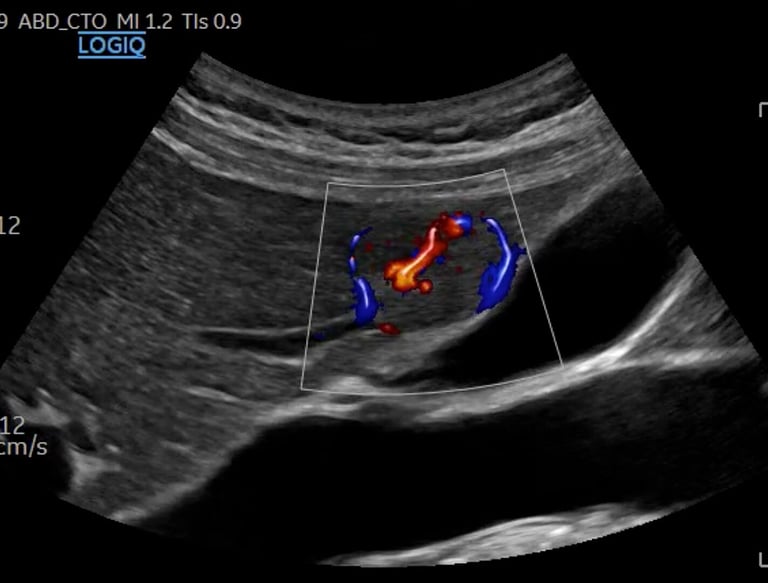

General Scans

Comprehensive radiological ultrasounds tailored to your health needs.